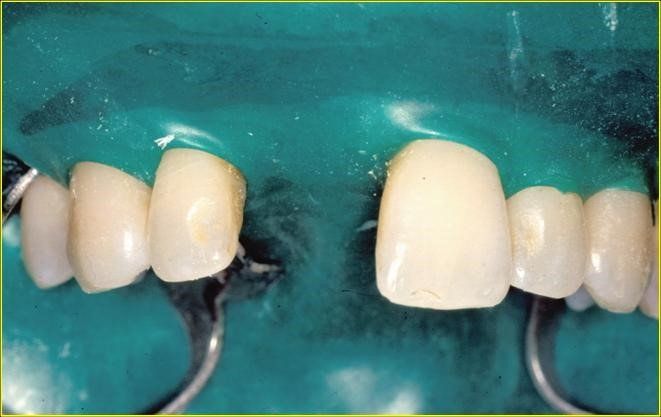

Arcata superiore destinata all’estrazione di tutti gli elemti dentali residui.

Una giovane signora di ventotto anni subisce nel 1996 la frattura dell’incisivo centrale superiore destro

in precedenza trattato endodonticamente